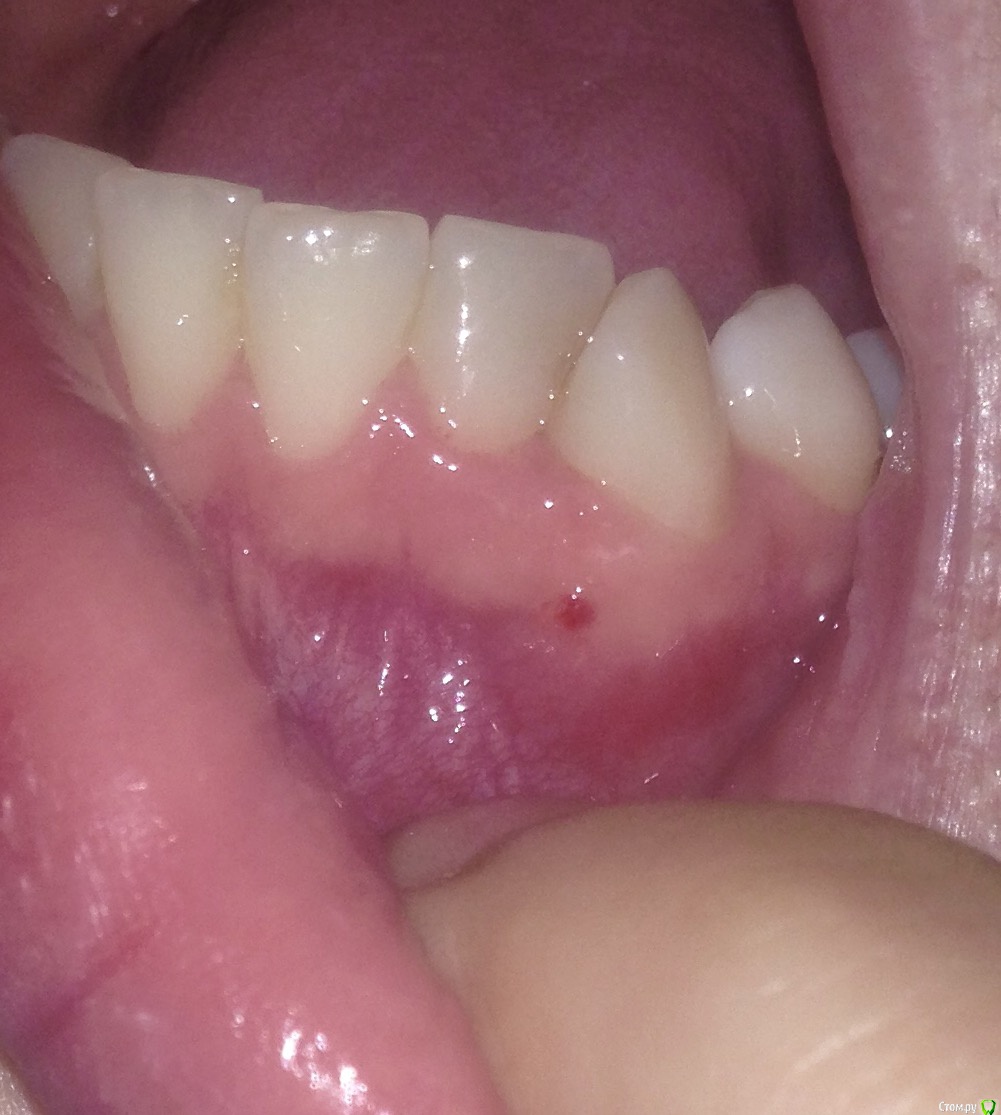

Юл1. Опубликовано 19 мая, 2020 Поделиться Опубликовано 19 мая, 2020 Здраствуйте, в хирургии была тема, но хотелось бы ещё мнения послушать. Случайно обнаружили в феврале этого года такой зуб, клиник много посетила, никто лечить не берёт. Две недели назад образовался прыщик, лопнул вчера, сейчас нет ничего, мазала метрогилом и полоскала хлоргексидином. Кт делала, ничего там особенного нет, не могу показать, не умею. Зуб абсолютно не болит. Интересует что это за прыщик был? Свищ? Бессимптомный периодонтит? Спасать зуб не буду, все в один голос говорят что шансов нет лезть в канал. Буду удалять если сломается. Вот что тогда делать? Имплант не встанет, брекеты финансово не смогу поставить, мост не хочу. Есть ли ещё какие варианты протезирования пусть даже не очень надёжного? Ссылка на комментарий

Юл1. Опубликовано 19 мая, 2020 Автор Поделиться Опубликовано 19 мая, 2020 (изменено) Действительно свищ, опять набралось, записалась к врачу, будем что то решать. Изменено 19 мая, 2020 пользователем Юл1. Ссылка на комментарий

Юл1. Опубликовано 23 мая, 2020 Автор Поделиться Опубликовано 23 мая, 2020 (изменено) Спасибо всем убедили спасти, вчера зуб лечили болит конечно сильно, через неделю уберут лекарство и временную пломбу. Изменено 23 мая, 2020 пользователем Юл1. Ссылка на комментарий